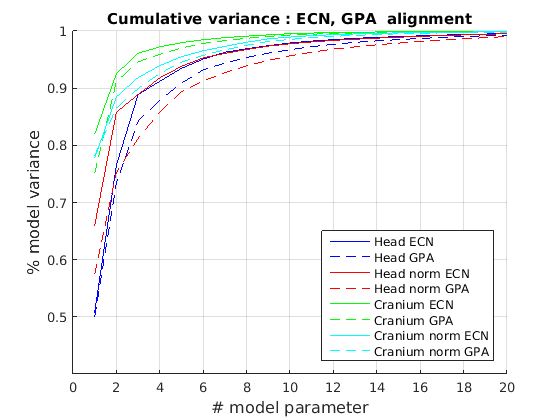

6.2 Model compactness

We evaluate both model construction with geometric alignment (ECN normalisation) and model construction with alignment by Generalised Procrustes Analysis (GPA). Model compactness is a key performance criterion for the correspondence and alignment processes that generate that model [31]. A more compact model has a smaller variance and requires fewer parameters to express a particular shape instance than less compact model. Cumulative variance plots generated by application of PCA are a useful measure of compactness, with more rapidly rising curves indicating more compact models. In Fig. 23 and Fig. 24 we present the cumulative variance plots for our profile models using automatic and manual landmarking respectively and aligned with either ECN or GPA alignment schemes.

Comparing the compactness of the models produced by automatic and manual facial profile landmarking, we found that the performance is almost identical and there is no statistical significance in performance given the modest test size of 100 faces. For example, for the full head profile, with no scale normalisation, the automatic landmarks give cumulative variances of 51.5%, 76.5%, 88.9% and 91.3% over the first four modes whereas the manual landmarks give 50.8%, 76.5%, 88.9% and 91.2%.

A point to note is that whatever model is built, ECN always produces more compact models than GPA. The difference is more marked when a head model is built (cranium and face) compared to cranium only. This can be explained by the fact that the cranium has 210 points sampled on its surface, whereas the face has 128. ECN focusses on aligning the majority group (cranial points) and does not allow more extreme features (such as a large nose) to influence this. GPA on the other hand does, so relatively few points around the nose region can influence alignment over the whole cranium. ECN normalisation is more appropriate when we are interested in cranial shape.